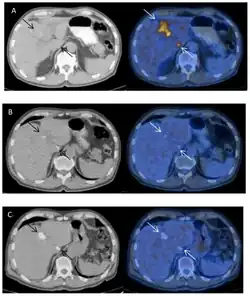

Zobrazovací metody

Alveokokové léze na játrech jsou viditelné pomocí řady zobrazovacích metod. Používá se ultrazvuk, MRI nebo CT. Moderní přístup v diagnostice AE nabízí i kombinované metody jako je PET/CT či PET/MRI.[43] PET diagnostika s využitím (18F)-fludeoxyglukózy je založena na zvýšeném metabolismu glukózy buněk na okraji cyst kvůli aktivní zánětlivé reakci.[64]